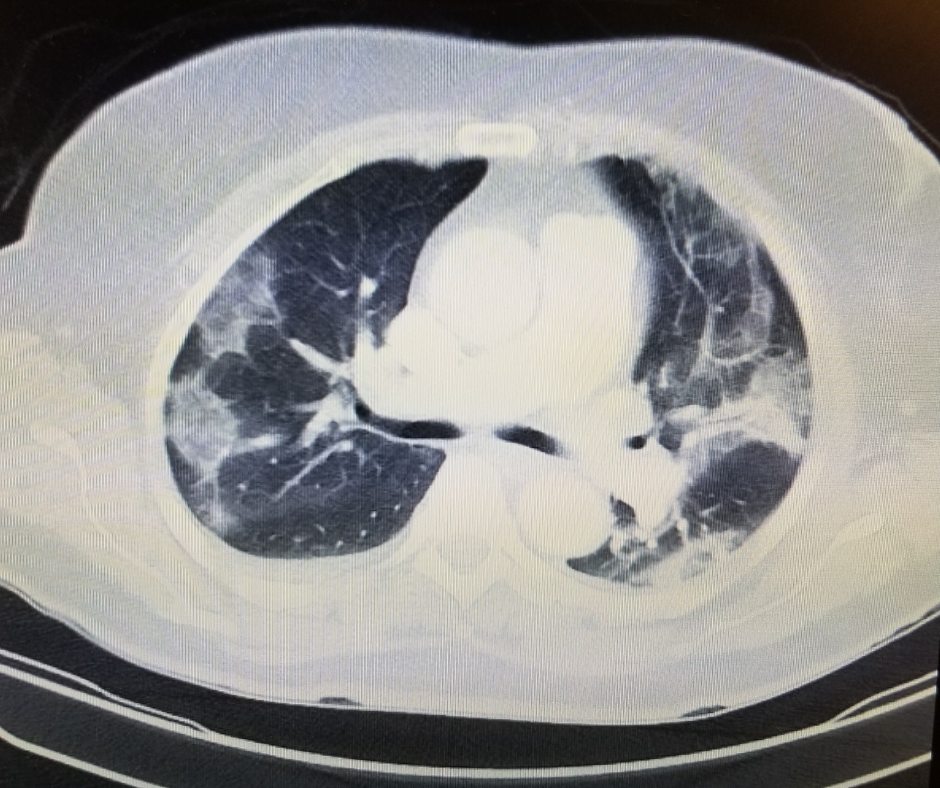

In their review of follow-up chest computed tomography (CT) scans, researchers from Wuhan, China found that nearly 40 percent of patients had interstitial lung abnormalities two years after having COVID-19.